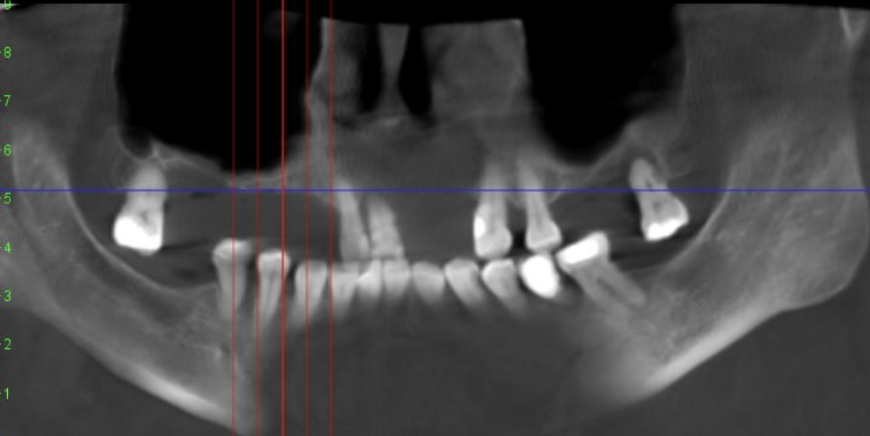

Имплантация зубов на сегодняшний день является лучшим решением для замены утраченных зубов. Зубные имплантаты решают сразу несколько задач: восстанавливают жевательную функцию, помогают вернуть красоту улыбки и сохранить здоровье полости рта. Хотите разобраться, что именно происходит на каждом этапе установки имплантов? Давайте заглянем в процесс шаг за шагом. Путь к красивой и здоровой улыбке начинается с приема и диагностики у врача-стоматолога-имплантолога. Сначала собираются жалобы, обсуждаются ожидания, проводится осмотр и дополнительные исследования: После диагностики врач составляет подробный план: где будет установлен имплант, какой вид и размер выбрать, и какая ортопедическая конструкция подойдет в конкретном случае. В клинике «Академия» при планировании имплантации мы используем 3D-моделирование и навигационные шаблоны, что обеспечивает точность и предсказуемость постановки имплантов. Перед тем как поставить зубной имплант, обязательно проводится профессиональная гигиена пол